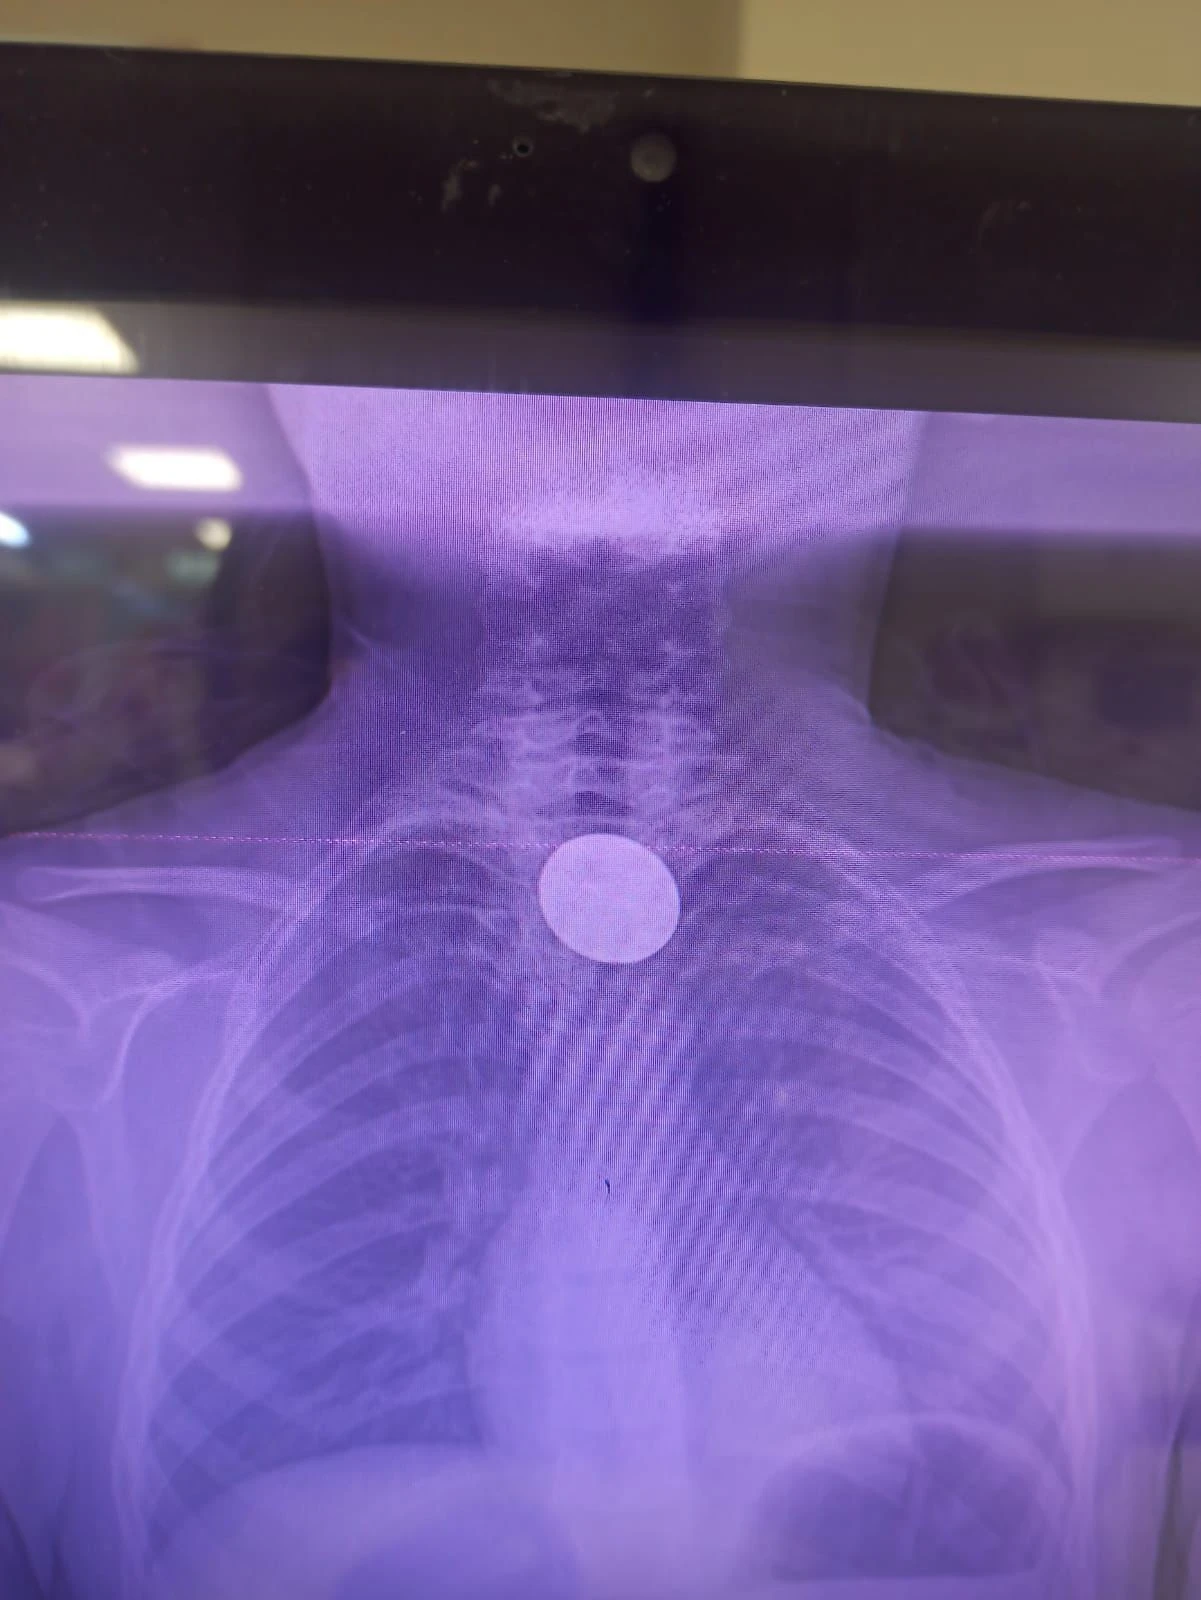

Tetkiklerde, 5 TL’lik madeni paranın yemek borusuna kadar ilerlediği belirlendi. Bunun üzerine Gastroenteroloji Uzmanı Dr. Yaren Dirik ile Kulak Burun Boğaz (KBB) Hekimi Dr. Yasin Gökçınar’ın ortaklaşa gerçekleştirdiği girişimle madeni para, herhangi bir komplikasyona yol açmadan çıkarıldı.

Siirt Eğitim ve Araştırma Hastanesi Başhekim Yardımcısı Uzman Dr. Burak Özkan, çocuk hastalarda yabancı cisim yutma vakalarının ciddi riskler taşıyabildiğine dikkat çekerek, “Hastanemize başvuran 8 yaşındaki hastamızın yemek borusuna kaçan madeni para, gastroenteroloji ve KBB ekiplerimizin titiz ve koordineli çalışmasıyla başarıyla çıkarılmıştır. Operasyon sorunsuz geçmiş, hastamızın genel durumu iyidir,” dedi.